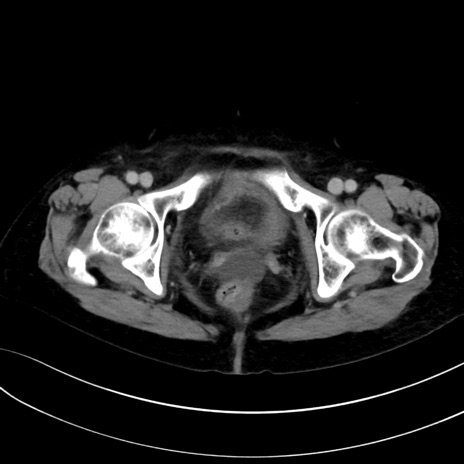

症例13 CT(横断像)1日半後